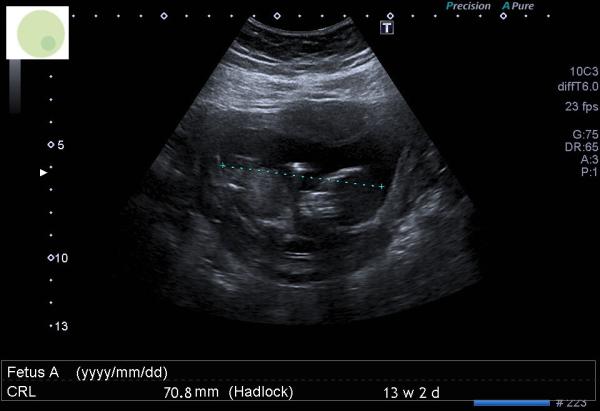

Hallo liebe Community, ich bin überglücklich, euch von unserem Ersttrimesterscreening zu berichten! Es war ein unvergesslicher Moment, unser kleines Wunder auf dem Bildschirm zu sehen. Der Arzt hat zwar das Geschlecht nicht ganz klar kommuniziert, aber er hat uns angeregt, schon mal einen Namen für [das Geschlecht] zu finden, was uns ein Gefühl von Sicherheit gegeben hat. Ich kann nicht anders ständig drauf zu gucken weil er auch sagte: ,,alles sieht gut aus, ich mache gute Arbeit in der Versorgung obwohl ich eig kaum Fisch esse🙈. Was meint ihr was ihr da sieht? Mein Freund ist in der Meinung der Arzt hätte lieber andere schöne Bilder nehmen solln😅🙈

Huhu, ja das erste Screening ist wirklich unfassbar aufregend. Also das Geschlecht kann ich wiklich garnicht erkennen. Liebe Grüße

Hello :) vom Köpfchen her würde ich auf einen Jungen tippen? 🤔🩵